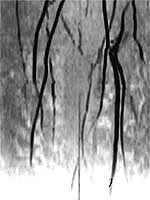

leg artery before gene therapy leg artery after gene therapy

New blood vessel growth in the leg is shown on the right, the result of gene therapy (courtesy of Dr. Jeffrey Isner, St. Elizabeth's Medical Center, Boston)